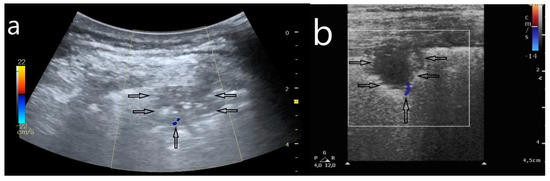

- (2)

- Artifacts: multifocally located single B-line artifacts, multifocal multiple (confluent) B-line artifacts, bilateral and symmetrical B-lines, white lung, spared areas;